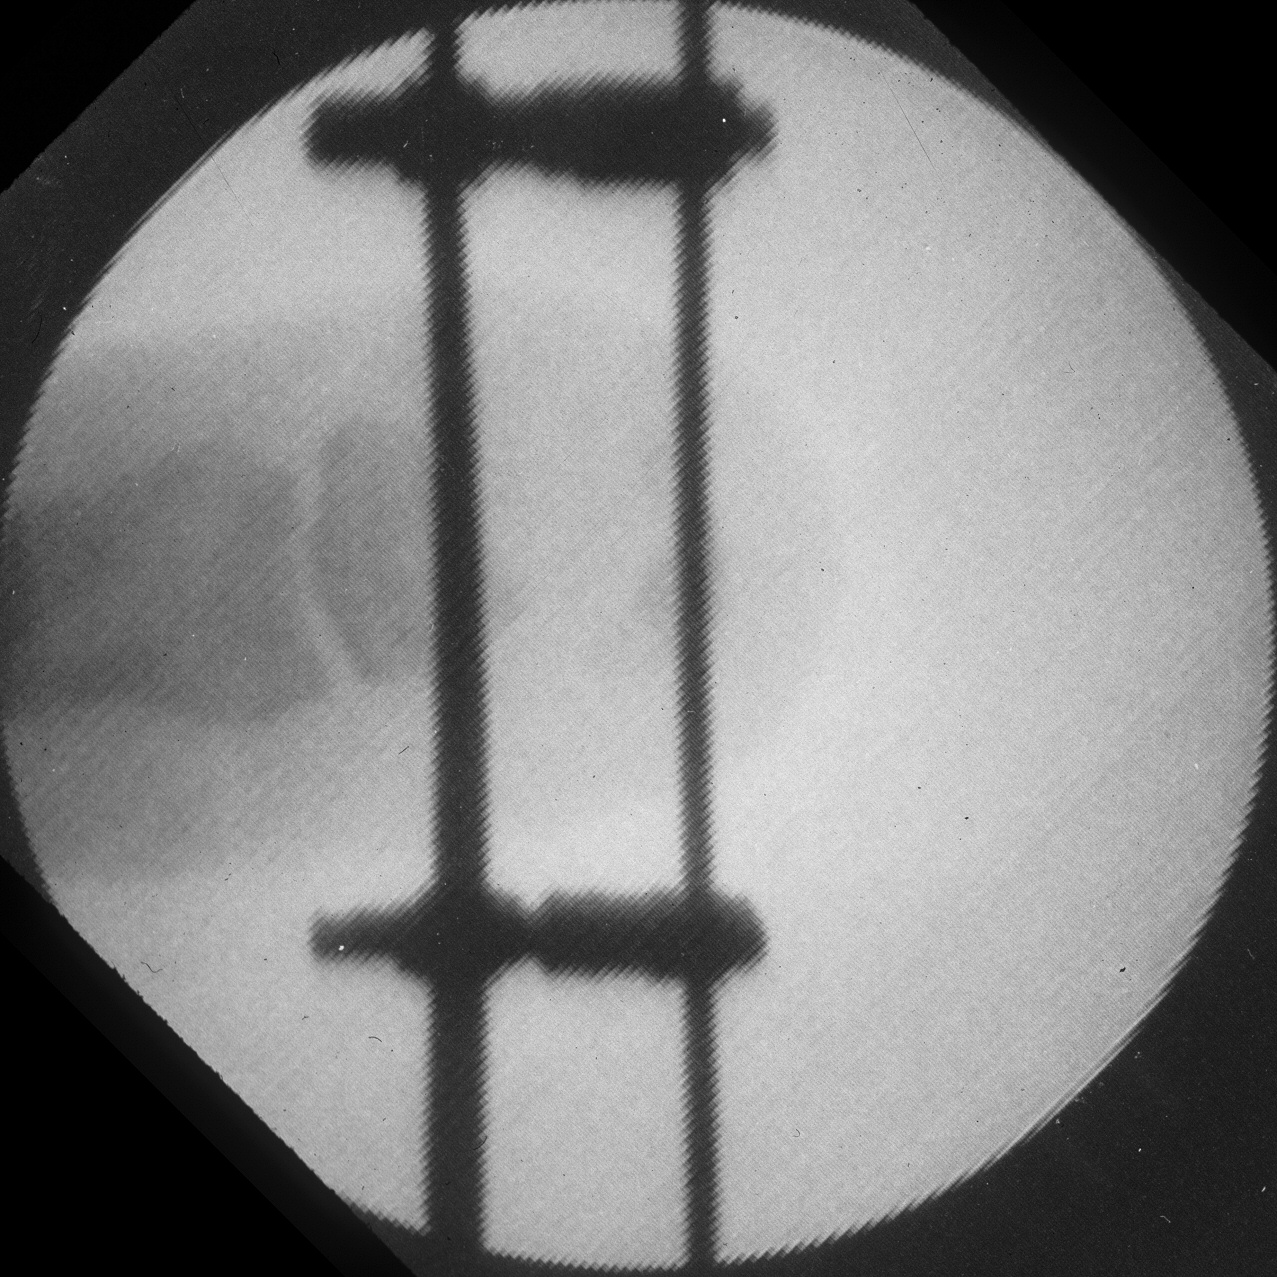

After two weeks of distraction:

Image Image Image